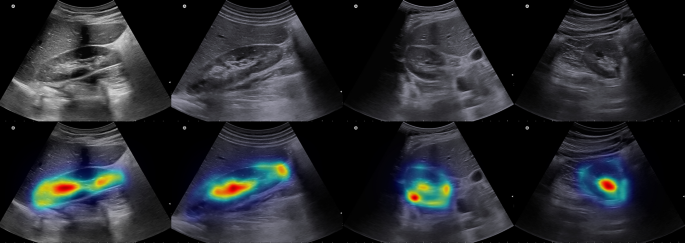

To enhance the interpretability of the proposed Fast-Unet++ architecture, we applied grad-CAM analysis to visualize the model’s activation patterns and identify the regions that contribute most significantly to the segmentation predictions. The results are visualized in Fig. 5.

Grad-CAM analysis results in some samples of sagittal and axial images. Top row is the original images and bottom row is the resulted grad-CAM analysis.

In this study, we proposed a novel CNN-based model for kidney segmentation from ultrasound images in sagittal and axial views and predicting kidney image biomarkers and volume. As far as we know, this is the first attempt to predict three kidney dimensions in addition to its volume and parenchymal thickness. We developed our previously published model, Fast-Unet39, by adding nested layers inspired by Unet++47. Compared with these networks, Fast-Unet++ takes advantage of the low computation cost of Fast-Unet and nested layers of Unet++. Therefore, combining these two structures yields better results, as reported in Table 1. Fast-Unet, however, performed better than Unet++, explainable by the intrinsic features of its architecture. As quantitative and qualitative results show, segmentation of the kidney in the sagittal frame yields more satisfying results due to the clearer borders of the kidney in these images. Thus, this project did not use an axial view for parenchymal thickness, as some radiologists do. In addition, the grad-CAM results demonstrate that the model effectively focuses on the kidney region, with high activation values highlighting the key anatomical features that guide the segmentation process. This analysis provides valuable insights into the model’s decision-making process and reinforces its ability to accurately segment the kidney in ultrasound images.